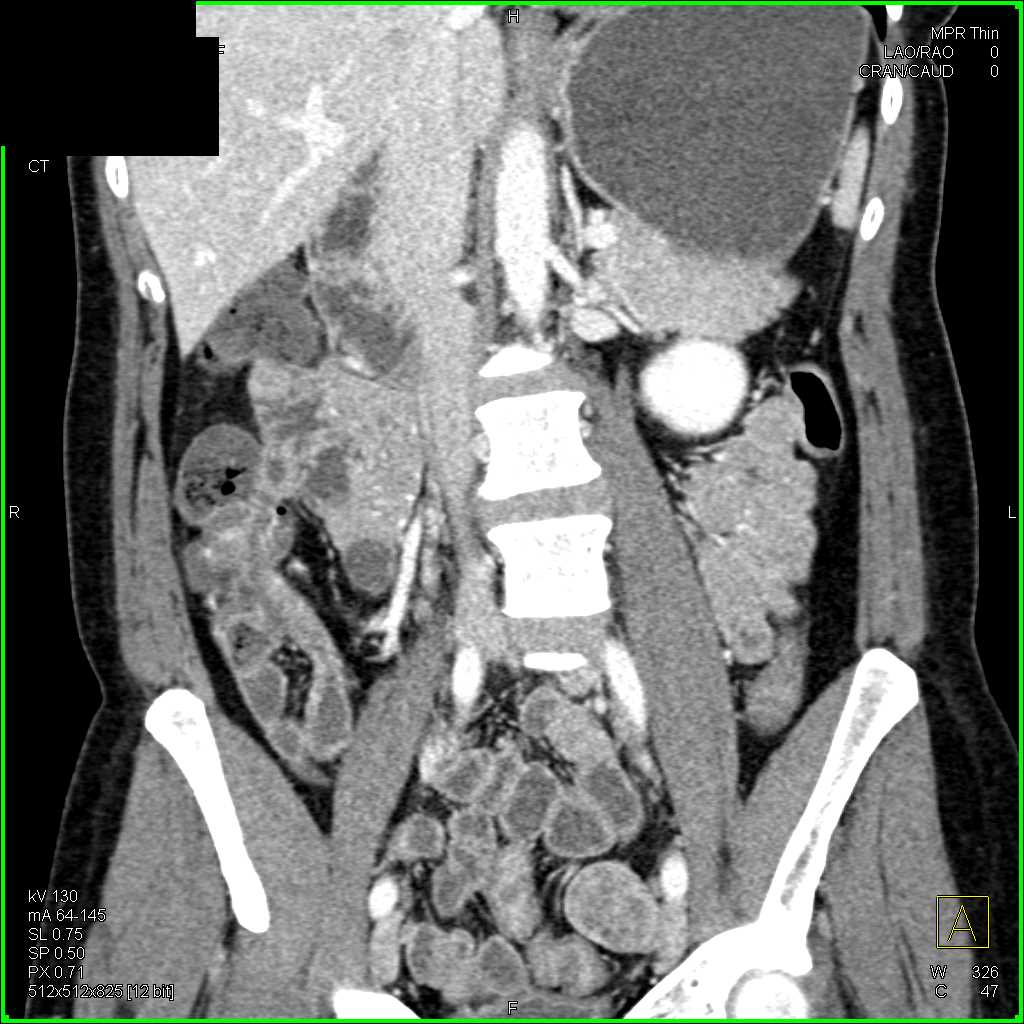

Crohns Disease Terminal Ileum